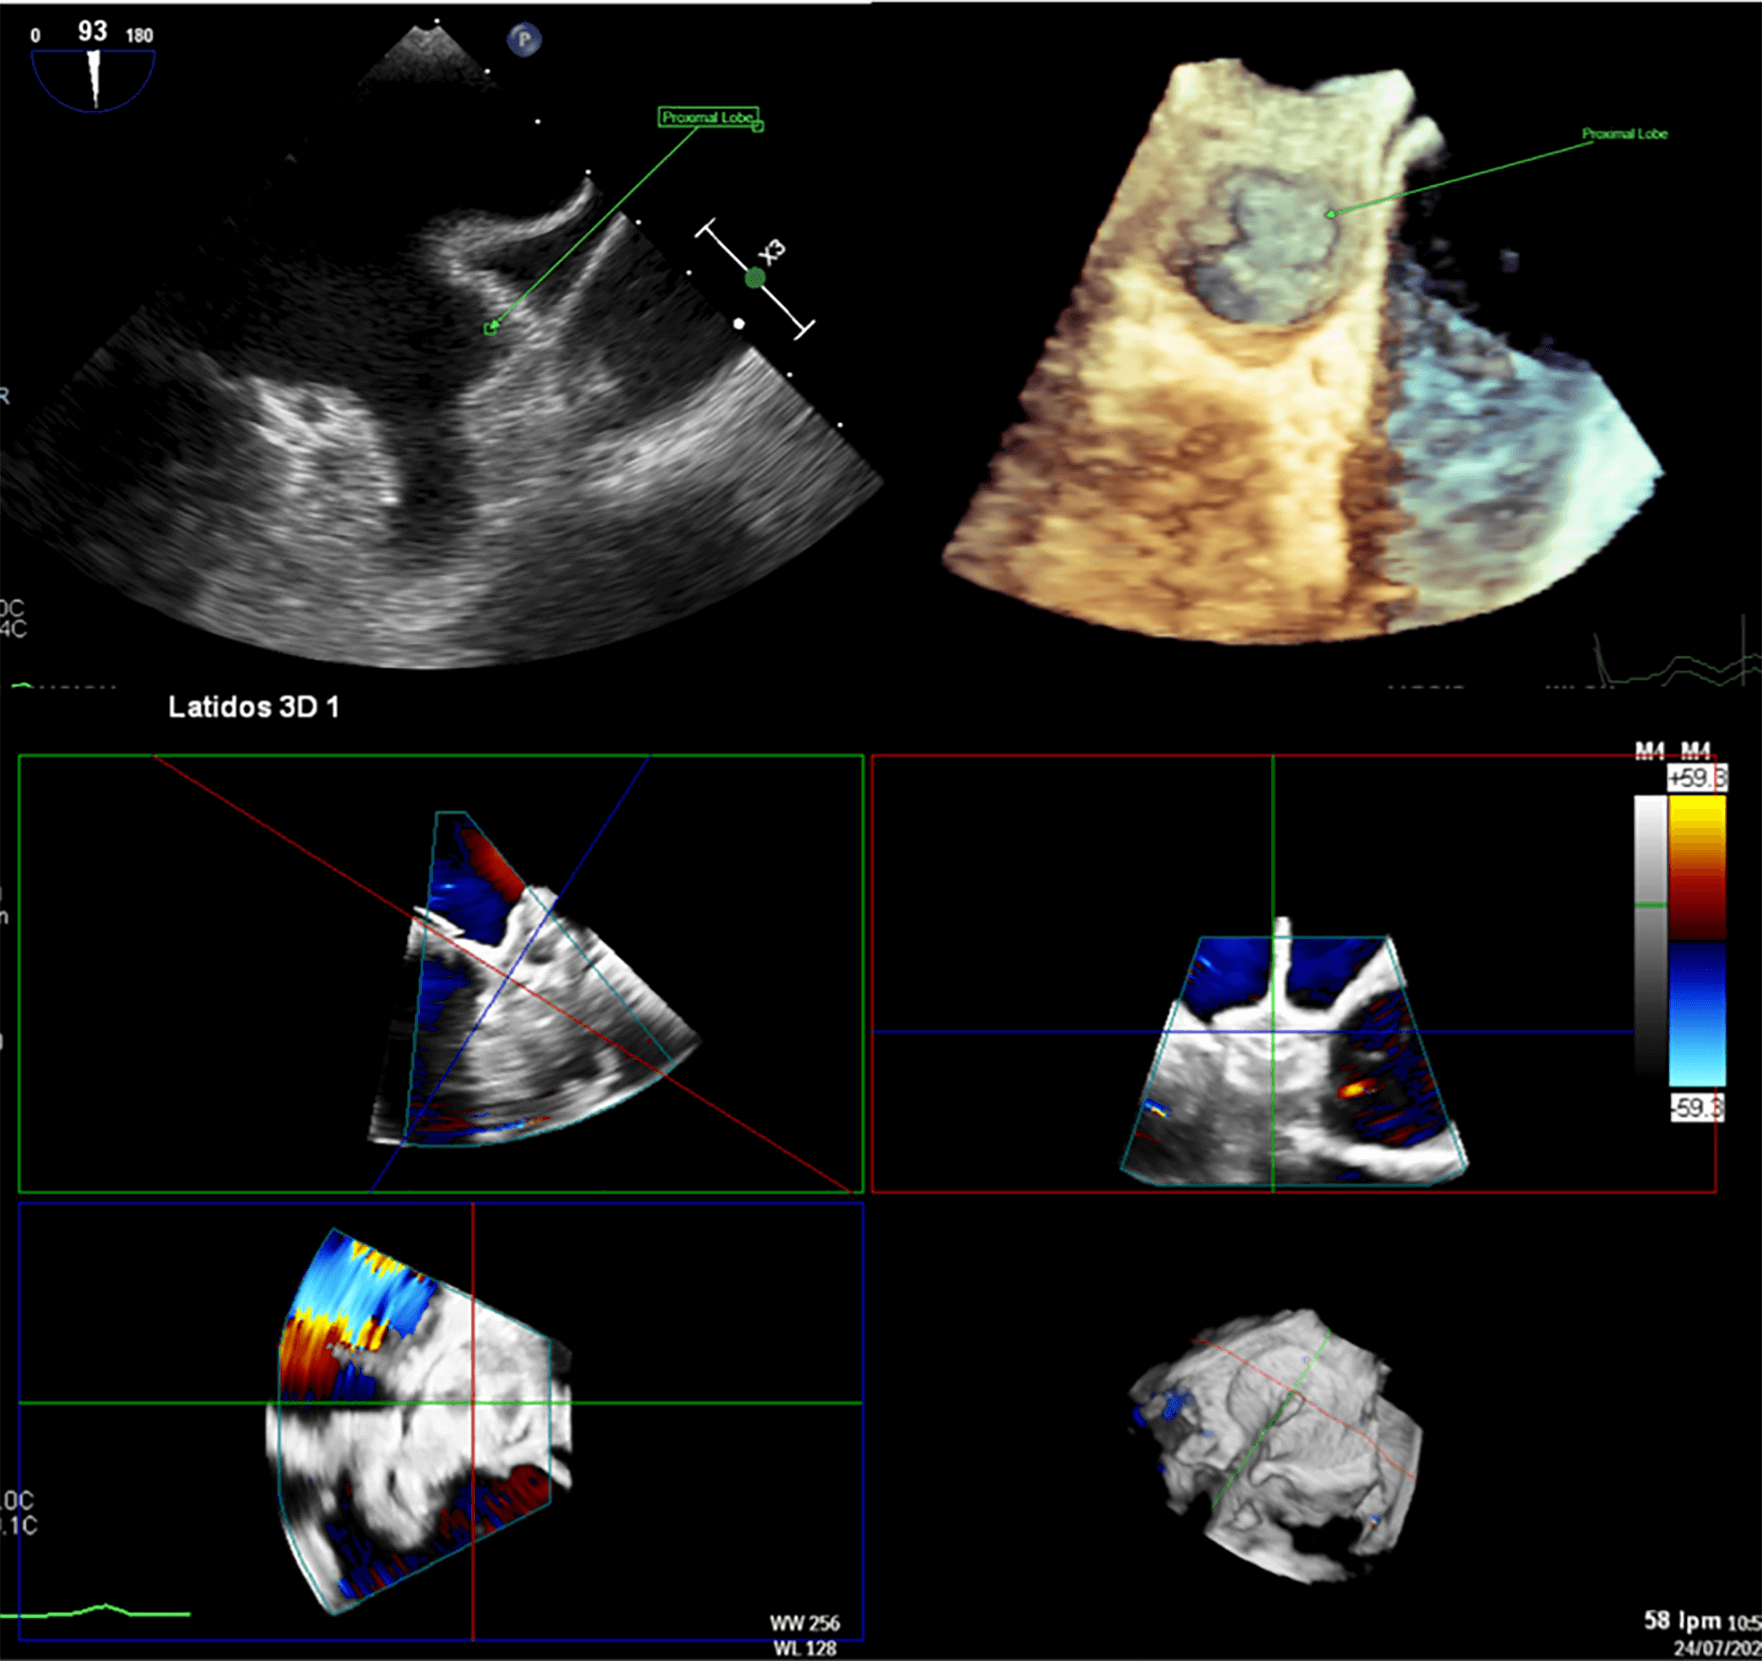

Fig. 4.

Left atrial appendage closure (LAAC) in a patient with complex anatomy. Transesophageal echocardiography (TEE) revealed a left atrial appendage (LAA) with a large proximal lobe, presenting a challenge for percutaneous closure. Nevertheless, an Amulet device was deployed successfully, with the lobe of the device positioned in the proximal lobe of the LAA and the disc effectively sealing the anatomical ostium.